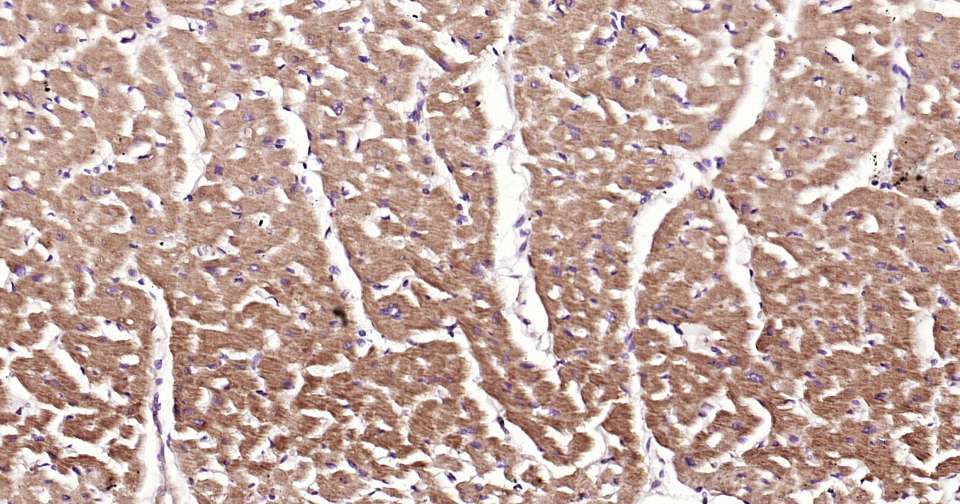

Immunohistochemical analysis of paraffin embedded human heart tissue slide using IHC0334H (Human ASK1 Kit).